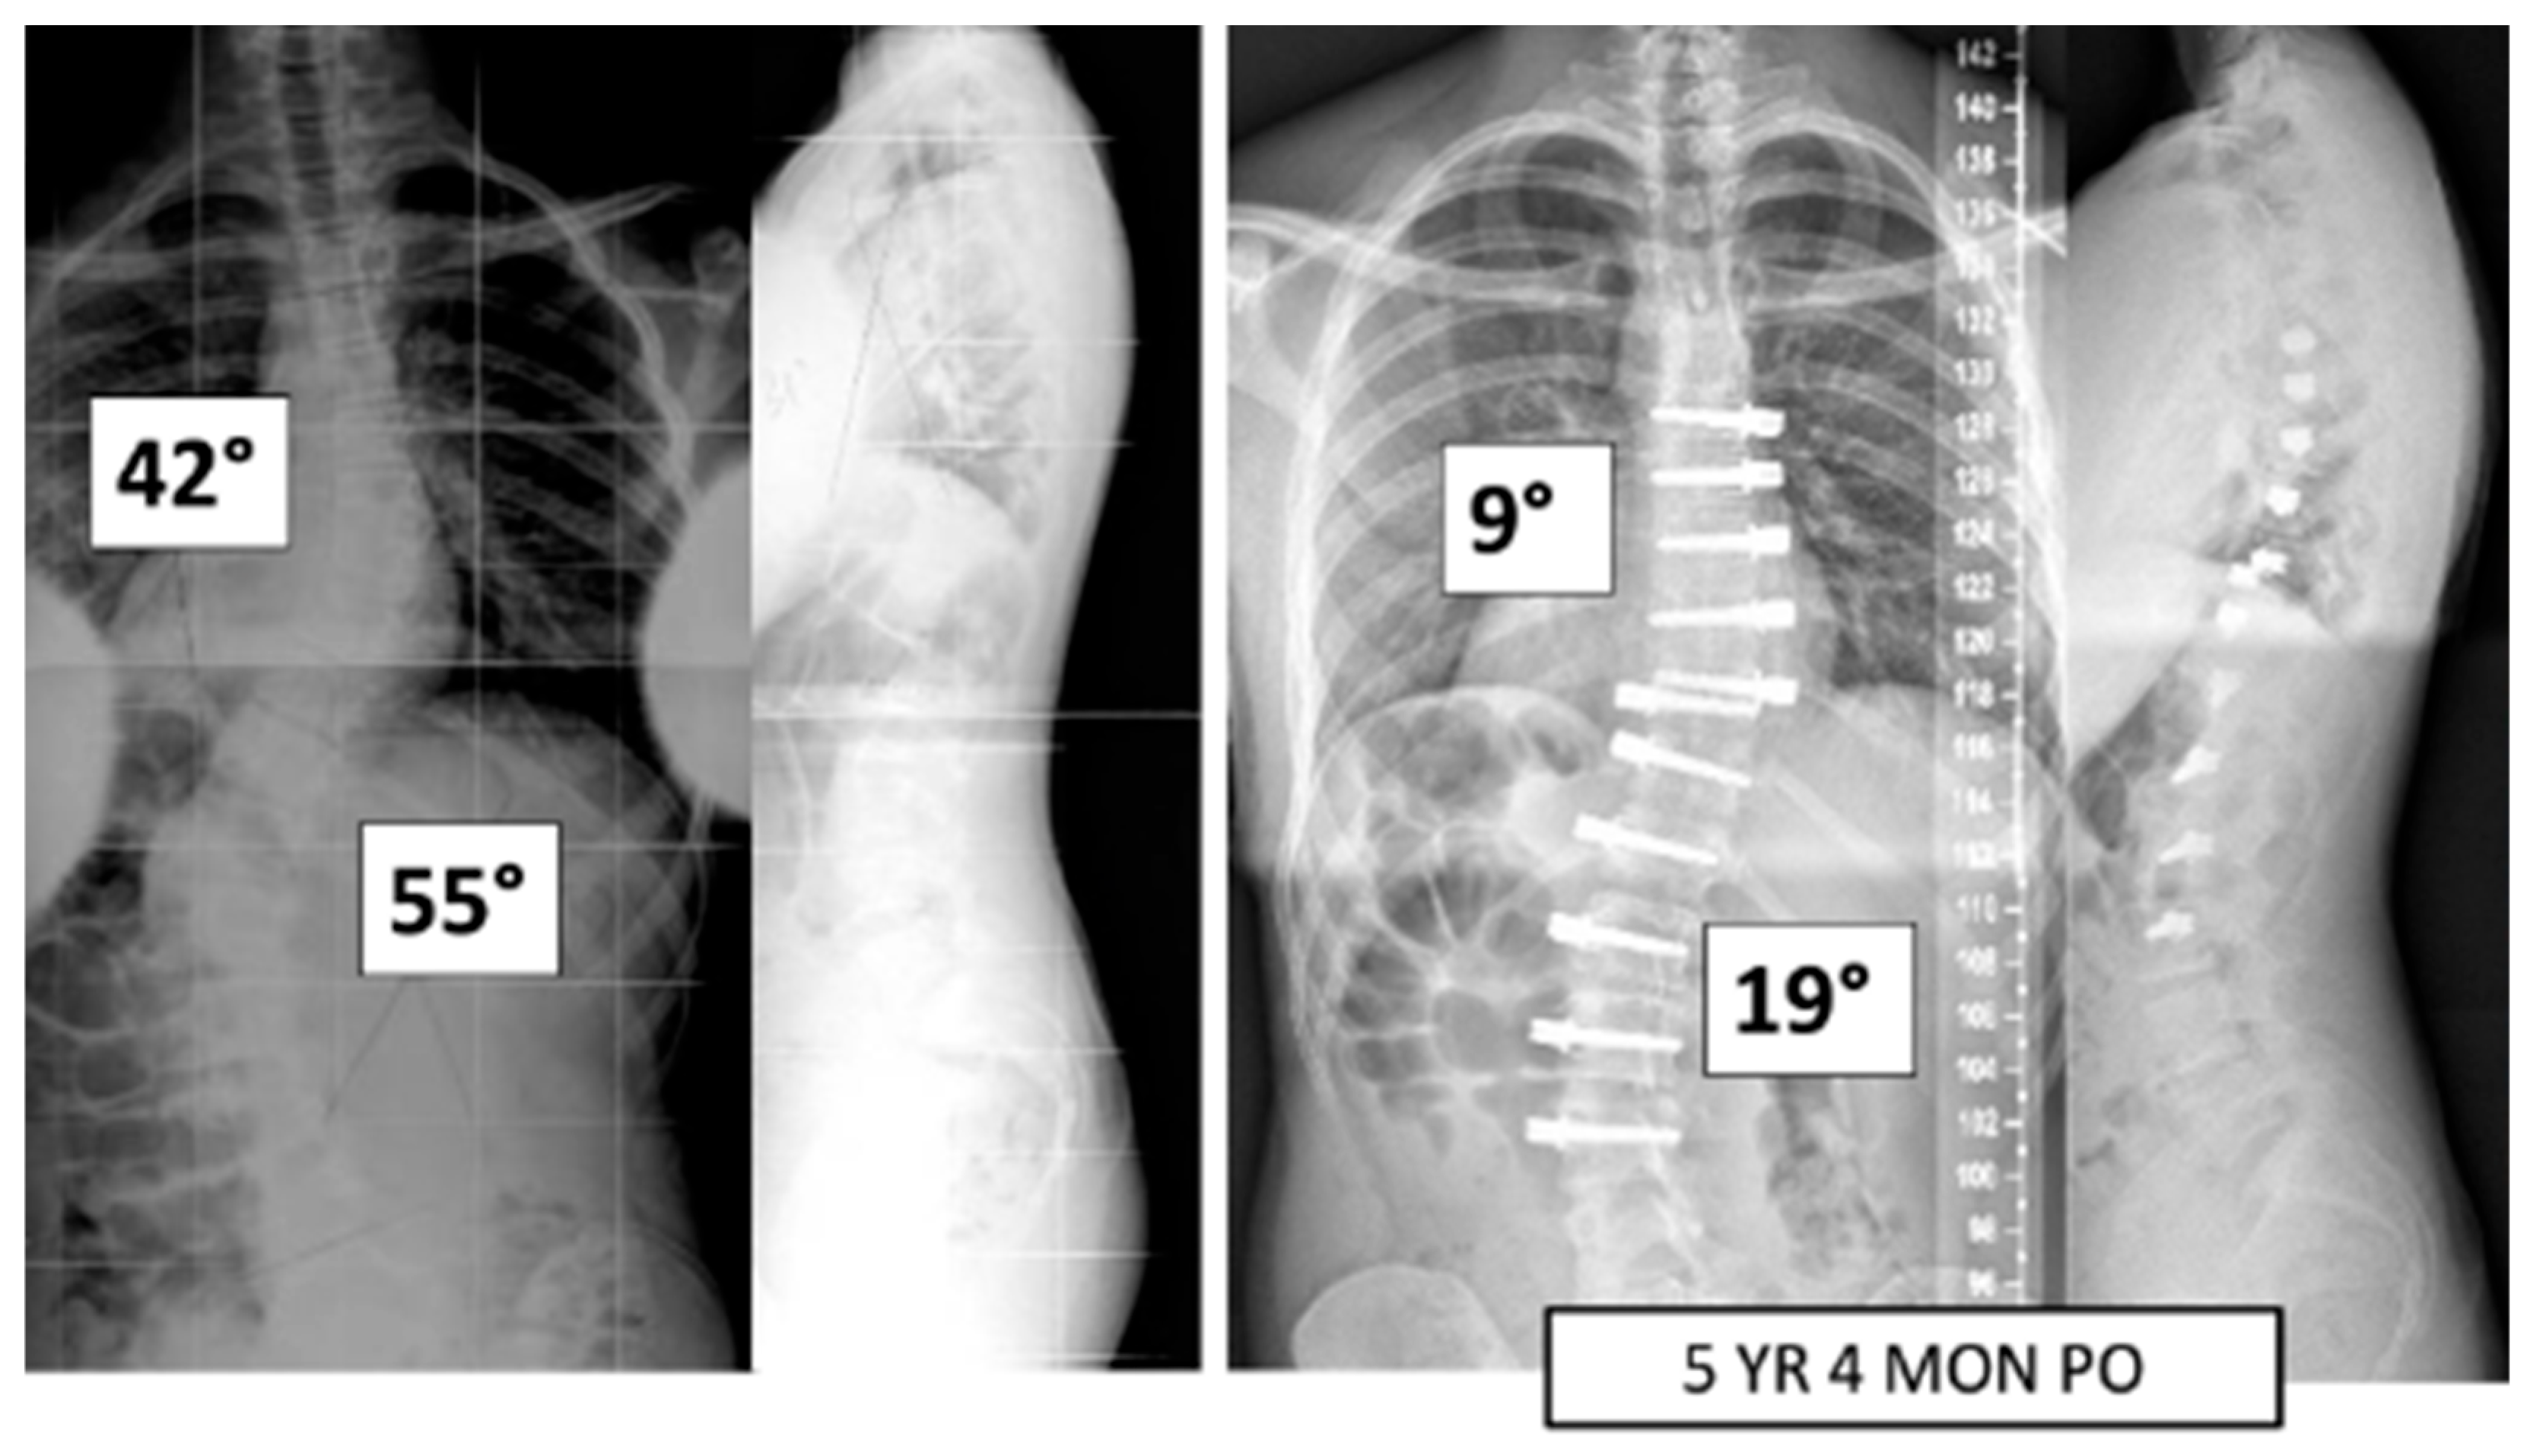

A total of 37 patients, age 14.1 ± 1.6 years, 86.5% female (Table 1), were included. Pre-operative major Cobb was 51 ± 8° and minor Cobb was 37 ± 13° (Figure 1 and Figure 2). Of the 27 Lenke 5 patients, 6 (22%) had their thoracic curve instrumented in addition to their thoracolumbar curvature. Of the 10 Lenke 6 patients, 9 (90%) had their thoracic curve instrumented as well. The mean FU was 35.9 ± 11.5 months.

Figure 1.

This is a 15-year-old male treated with bilateral VBT instrumentation. At 5 years and 4 months post operation, he has returned to all activities.